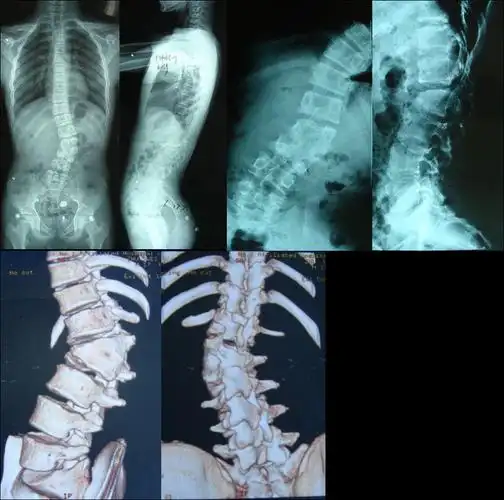

先天性脊柱侧弯2半椎体畸形